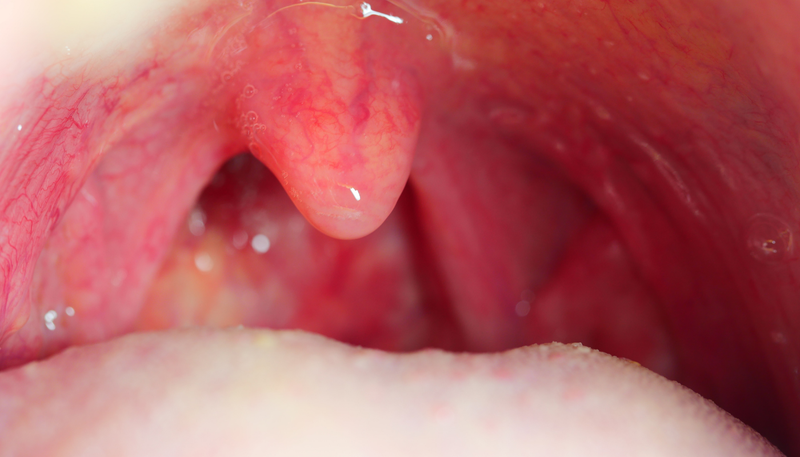

Viêm amidan có thể gây ra nhiều vấn đề cho đường hô hấp, như đau họng, khó nuốt, và ngưng thở khi ngủ. Phương pháp điều trị ban đầu thường được khuyến nghị là chăm sóc tại nhà, bao gồm chế độ dinh dưỡng hợp lý và cải thiện lối sống. Nếu viêm amidan do vi khuẩn, bác sĩ có thể kê đơn kháng sinh để điều trị. Trong trường hợp viêm amidan tái phát nhiều lần, phẫu thuật cắt amidan có thể là giải pháp được xem xét.

Phẫu thuật này nhằm mục đích loại bỏ hoàn toàn amidan khẩu cái thông qua một vết mổ xung quanh amidan, giữa mô amidan và cơ thành họng. Những người thường xuyên gặp phải triệu chứng như đau họng, ngưng thở khi ngủ, hoặc ngáy do viêm amidan có thể được chỉ định phẫu thuật. Tuy nhiên, trước khi quyết định, bác sĩ sẽ xem xét nhiều yếu tố như tuổi tác, nguyên nhân viêm, mức độ nghiêm trọng của tình trạng, cũng như ảnh hưởng đến sinh hoạt và sức khỏe của bệnh nhân.